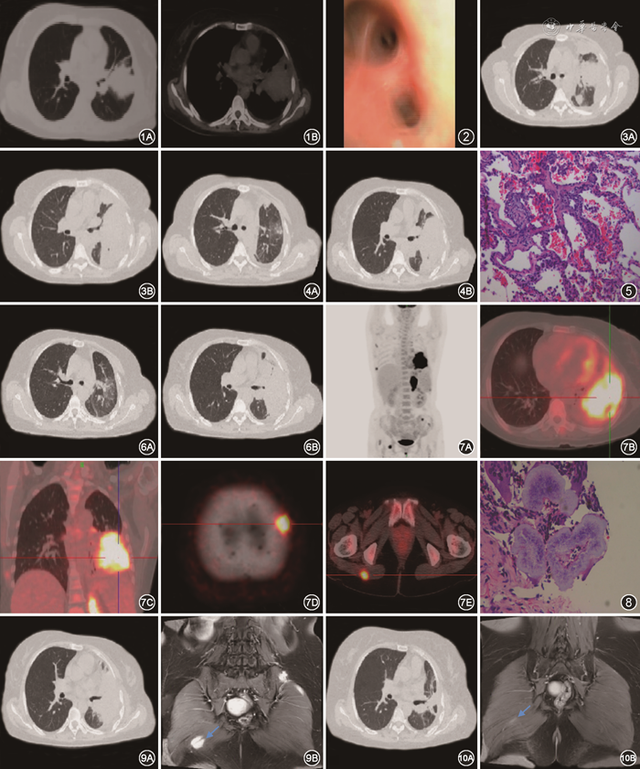

患者女,47岁,因“咳嗽、咳痰、痰中带血50 d,加重伴发热15 d”于2022年2月18日入院。患者于2021年12月28日无明显诱因出现咳嗽、咳痰,痰中带血,为鲜红色,无发热、盗汗、胸痛等症状,自行口服抗感染药物(具体不详)后症状稍有缓解。2022年2月3日患者出现发热,测量体温为38 ℃,伴左侧胸痛,就诊于当地诊所,给予“左氧氟沙星、头孢”治疗后症状未见明显缓解,胸部CT示左肺上叶舌段占位性病变可能性大、累及下叶、伴左侧胸腔积液,左肺下叶基底段炎症( 图1 )。继续抗感染治疗后,未见明显好转。既往无慢性病及传染病史,无手术、外伤史,无输血史,无药物、食物过敏史,无吸烟、饮酒史。家族中无传染病及遗传病史。

图1 2022年2月10日外院胸部CT示左肺上叶舌段占位性病变可能性大、累及下叶、伴左侧胸腔积液,左肺下叶基底段炎症

图2 气管镜下可见左肺舌叶及下叶黏膜充血,未见明显新生物

图3 2022年2月24日胸部增强CT示左肺上叶占位,纵隔多发肿大淋巴结,左侧包裹性胸腔积液,相邻肺组织膨胀不全,少许心包积液

图4 2022年3月10日复查胸部CT可见病灶局部较前稍缩小

图5 肺穿刺病理回报:(左上肺)穿刺肺组织慢性炎伴急性炎,肺泡上皮增生,肺泡内见出血,局灶纤维组织增生,见少量肉芽肿病变 HE 高倍放大

图6 2022年5月9日胸部CT示左肺上叶病灶较前增大,周围渗出影增多,纵隔多发肿大淋巴结,左侧胸腔积液较前略减少

图7 2022年5月16日患者PET-CT示左肺占位性改变(图7A~7C),FDG摄取明显增高(图7B和图7C),伴左侧胸膜(图7A)、全身多发淋巴结(图7A)、胰体部(图7A)、骨骼(图7D)、多发肌肉(图7E)受累

图8 臀部肌层病理回报:(右侧臀大肌)穿刺肌肉及纤维慢性炎伴中度急性炎及微脓肿形成,局灶查见数个菌落样结构及多核巨细胞 HE 高倍放大

图9 2022年9月16日复查胸部CT(图9A)及腹部增强MR(图9B)提示左肺及臀大肌病灶(箭头所示)较前明显吸收

图10 2023年5月23日复查胸部CT(图10A)及腹部增强MR(图10B)提示肺部及肌肉病灶(箭头所示)持续缩小体检:体温38 ℃,脉率84次/min,呼吸20次/min,血压114/76 mmHg(1 mmHg=0.133 kPa)。右肺呼吸音正常,左肺呼吸音低,可闻及散在湿啰音。心腹未见明显异常。入院诊断:肺部阴影待查(感染?肿瘤?)

诊治经过:入院后动脉血气分析:pH值7.50,PaCO 2为38 mmHg,PaO 2为71 mmHg;血常规+生化:白细胞12.90×10 9/L,中性粒细胞10.80×10 9/L,C反应蛋白131.26 mg/L;丙氨酸转氨酶54.4 U/L,天冬氨酸转氨酶39.8 U/L,白蛋白25.3 g/L;肿瘤全套:CA125为59.20 U/ml,CA72-4为27.00 U/ml,FE为698.9 μg/L,余未见明显异常;细胞+多因子:淋巴细胞亚群绝对值及占比均正常,IL-6为111.56 ng/L,C3、C4及补体正常;结核等相关检查未见明显异常。因此,给予盐酸莫西沙星联合头孢哌酮钠舒巴坦钠经验性抗感染及对症支持治疗。支气管镜检查+肺泡灌洗( 图2 ):双侧支气管可见黏性分泌物,左肺舌叶及下叶黏膜充血。灌洗液床旁快速病原菌鉴定(简称M-ROSE)提示:细菌,偶见杆菌,巨噬细胞1.65%,中性粒细胞97.80%。微生物宏基因组二代测序(metagenomics next generation sequencing,mNGS)结果回报:gipuzkoensis诺卡菌属(序列数303,置信度99%)。胸部增强CT( 图3 )提示:左肺上叶占位,考虑恶性伴阻塞性炎症可能;纵隔多发肿大淋巴结,转移不除外;左侧胸腔积液(包裹性)、相邻肺组织膨胀不全;少许心包积液。于2022年2月22日调整抗感染方案为磺胺甲噁唑/甲氧苄啶片(4片,3次/d)+亚胺培南/西司他丁钠(1 g,1次/8 h),2022年3月1日进一步行超声引导下胸腔闭式引流术。胸腔引流出脓血性液体约50 ml。化验回报:橘红色浑浊液体,比重1.034,蛋白定性试验阳性,细胞总数满视野,其中白细胞2 688×10 6/L,单核细胞38%,多核细胞62%;胸腔积液中蛋白50.5 g/L,氯96.94 mmol/L,糖1.59 mmol/L。多次送检血培养未见明显异常。于2022年3月10日复查胸部CT( 图4 ):病灶局部较前稍缩小。2022年3月11日行CT引导下经皮肺穿刺活检术。病理提示(图5):(左上肺)穿刺肺组织慢性炎伴急性炎,肺泡上皮增生,肺泡内见出血,局灶纤维组织增生,见少量肉芽肿病变。患者2022年3月23日出院,继续口服磺胺甲噁唑/甲氧苄啶片(2片,3次/d)。

2022年5月9日再次来院复诊,复查胸部CT示( 图6 ):左肺上叶肿块,较前增大,周围渗出影增多,纵隔多发肿大淋巴结,左侧胸腔积液较前略减少,相邻肺组织膨胀不全,少许心包积液。进一步行PET-CT提示( 图7 ):左肺占位性改变,FDG(氟代脱氧葡萄糖)摄取明显增高,考虑恶性可能,伴阻塞性肺炎、肺不张;左侧胸膜受累;伴全身多发淋巴结、胰体部、多发肌肉、骨骼受累。2022年6月10日超声引导下臀部肌层病灶穿刺取活检,病理回报( 图8 ):(右侧臀大肌)穿刺肌肉及纤维慢性炎伴中度急性炎及微脓肿形成,局灶查见数个菌落样结构及多核巨细胞。臀大肌肌肉活检组织mNGS示gipuzkoensis诺卡菌属,检出序列数(百分比):2 937(100%),置信度99%。至此患者诊断明确,考虑肺gipuzkoensis诺卡菌感染伴胸膜、肌肉、骨、胰腺等全身多部位播散。因此,治疗上继续给予磺胺甲噁唑/甲氧苄啶片(4片,3次/d)联合利奈唑胺(600 mg,1次/12 h)抗感染及碳酸氢钠片碱化尿液以及护肝、抑酸护胃等治疗,定期复查胸部CT、腹部及头颅增强MR,提示左肺、臀大肌病灶逐渐吸收( 图9 )。2022年10月因血小板减少调整抗感染方案为磺胺甲噁唑/甲氧苄啶片(4片,3次/d)单药治疗,定期复查肺部及臀大肌呈明显缩小趋势( 图10 )。